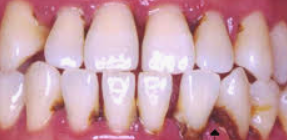

잇몸이 붓고 피가 나는 증상은 흔히 잇몸 질환의 신호일 수 있습니다. 이러한 증상을 겪고 있다면, 가장 먼저 해야 할 일은 구강 위생을 철저히 하는 것입니다. 다음은 잇몸 붓기와 출혈을 줄이는 데 도움이 되는 몇 가지 방법입니다:

이러한 방법들을 통해 잇몸의 붓기와 출혈을 줄일 수 있지만, 증상이 지속되거나 악화될 경우에는 반드시 치과 의사와 상담해야 합니다. 잇몸 질환은 초기에 치료할수록 더 좋은 결과를 얻을 수 있으므로, 증상을 무시하지 말고 적극적으로 관리하는 것이 중요합니다.